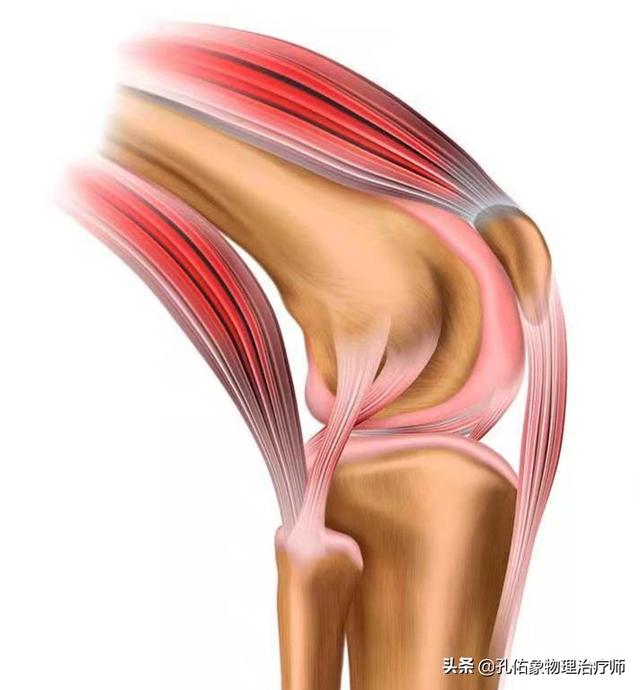

私たちの膝関節には内側と外側の2つの半月板があり、内側の半月板は内側側副靭帯と内側の関節包に、外側の半月板は外側の関節包に繋がっており、大腿四頭筋、半膜様筋、後方の膝窩筋も半月板に繋がっています。半月板は、関節窩の深さを深くし、太ももの骨とふくらはぎの骨の連結をより適応しやすくし、膝関節の安定性を高めるだけでなく、同時に膝関節を保護し、衝撃を和らげるクッションの役割も果たす、私たちの体にとって非常に重要な構造物です。

しかし、日常生活では半月板は見落とされがちだが、膝の痛みは何らかの形で半月板と関係している!.半月板をよりよく知るためには、半月板の栄養補給についても知っておく必要がある:

半月板に大きく依存している血液和関節包内の滑液(医学)半月板の外側1/3には血液が供給され、中心部にもわずかに供給されるが、内側1/3には血液がなく、主に関節包の滑液に栄養を頼っている。

半月板が変性していると、うっかりしゃがんだり立ち上がったりして体を回転させたときに、半月板が損傷することがある。明らかに、血液供給、クッション、滑液の問題が、冷たさ、痛み、動きに伴うガタつきの直接的な原因となっている。